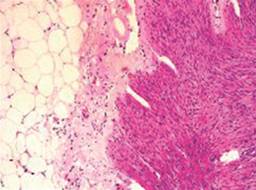

Los resultados histopatológicos del apéndice fueron apendicitis aguda del anciano con necrosis de la mucosa y submucosa (Figuras 1 a 4).

Figura 4: Apéndice cecal, diámetro y aspecto macroscópicamente normales. Observación macroscópica del apéndice opaca y demacrada y engrosamiento del mesoapéndice.